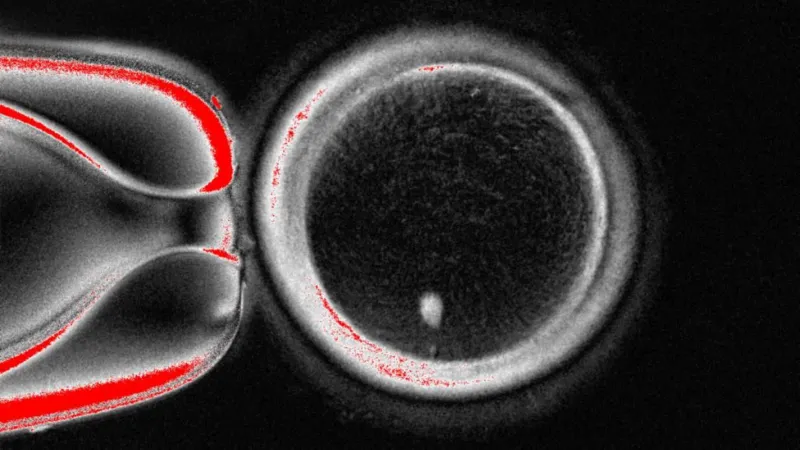

The big circle is the egg viewed under a microscope, the white dot at the bottom is the genetic material taken from a skin cell and placed inside

However, this egg is not ready to be fertilised by sperm as it already contains a full suite of chromosomes.